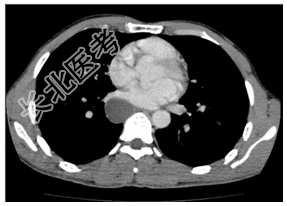

- [材料题] 患者,男性,31岁。阵发性胸痛多年,近来明显。查体:双肺呼吸音清,未闻及干湿性啰音。腹平软,肝脾未扪及。行胸部CT平扫及增强检查。

- 简答题1、患者的诊断及依据是什么?

- 简答题2、鉴别诊断有哪些?